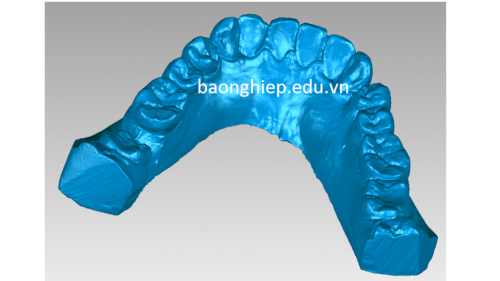

- Cống nghệ scan3d đáp ứng nhu cầu phục vụ trong ngành nha khoa chỉnh hình răng

Scan3d chỉnh hình răng hàm dưới